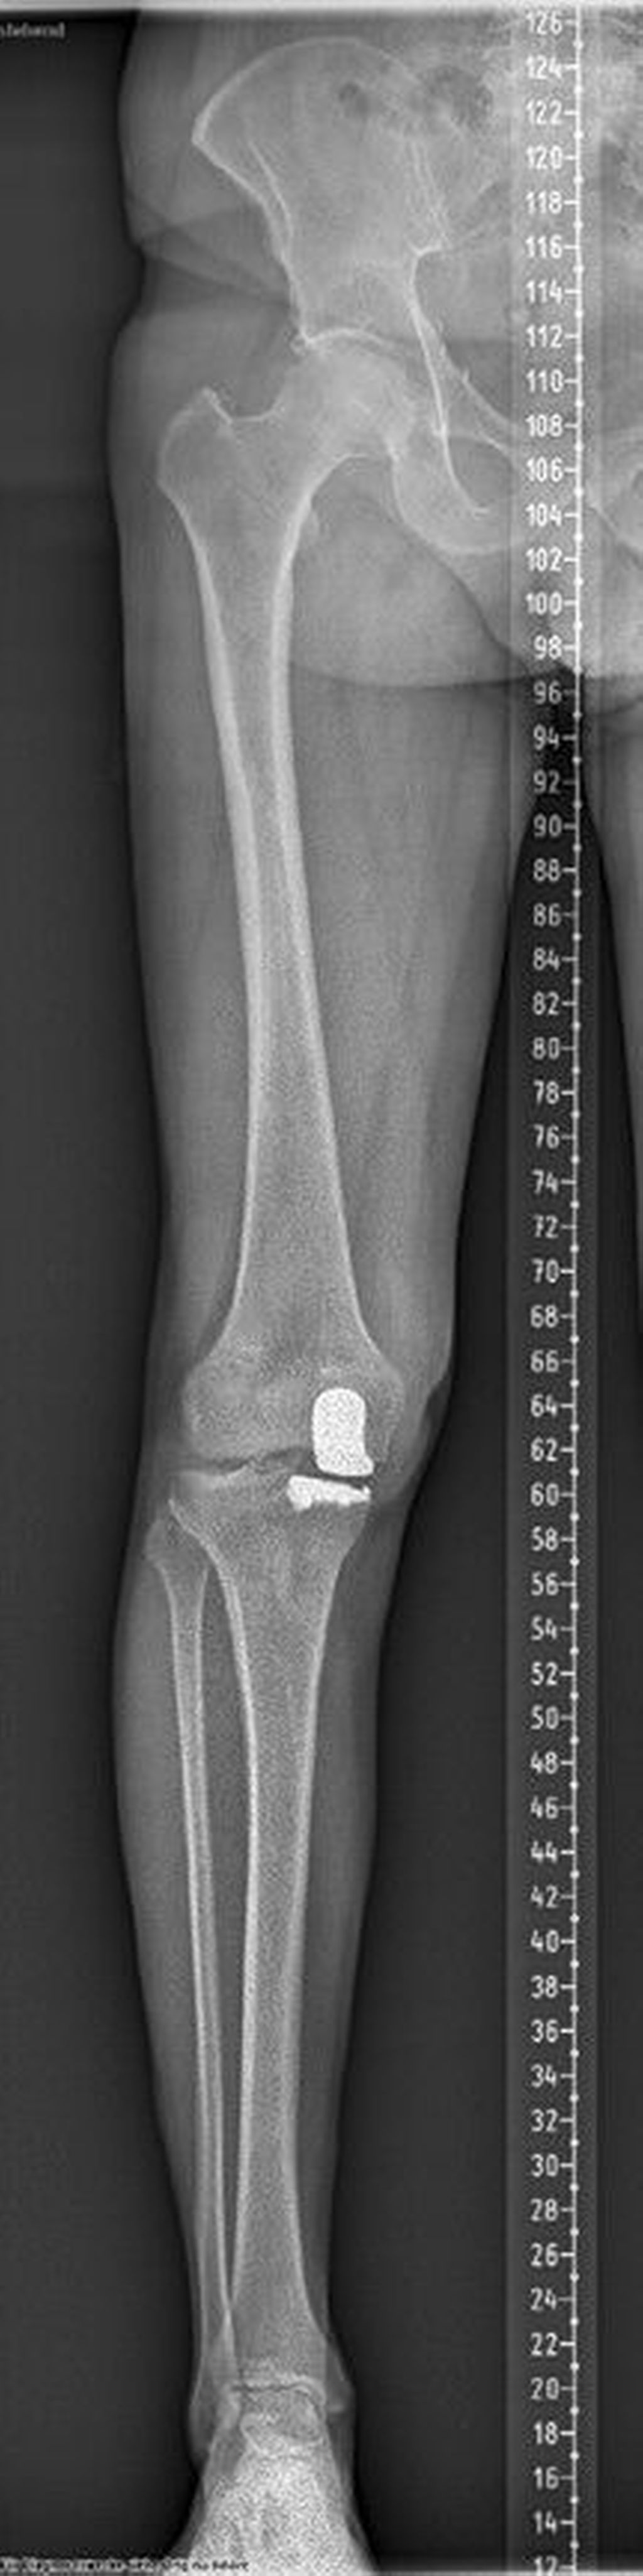

Ein 62-jähriger Patient stellte sich im März 2025 mit belastungsabhängigen Knieschmerzen rechts vor. Im MRT zeigte sich eine Läsion des medialen Meniskus, sodass in Zusammenschau mit dem positiven Meniskuszeichen in der klinischen Untersuchung eine partielle Meniskektomie durchgeführt wurde. Die postoperative Phase verlief zunächst unauffällig. Der Patient berichtete über ein beschwerdefreies Intervall von rund sieben Wochen. Anschließend entwickelten sich jedoch erneut zunehmende Schmerzen im rechten Kniegelenk, die eine erneute Vorstellung in der Spezialambulanz erforderlich machten. Er berichtete vor allem über belastungsabhängige Schmerzen im Bereich des medialen Kniegelenks. Daraufhin wurde ein Ganzbeinröntgen zur Beurteilung der Beinachse durchgeführt, hier zeigte sich eine varische Beinachse mit 5 Grad Varus (Abb.1). In der ergänzend durchgeführten MRT-Untersuchung konnte medialseitig eine ausgeprägte Nekrosezone am medialen Femurkondyl nachgewiesen werden (Abb.2). Schlussendlich wurde aufgrund dieses Befundes die Indikation zur Implantation einer medialen Hemischlittenprothese rechts gestellt, die schließlich im August 2025 komplikationslos durchgeführt wurde (Abb.3+4).